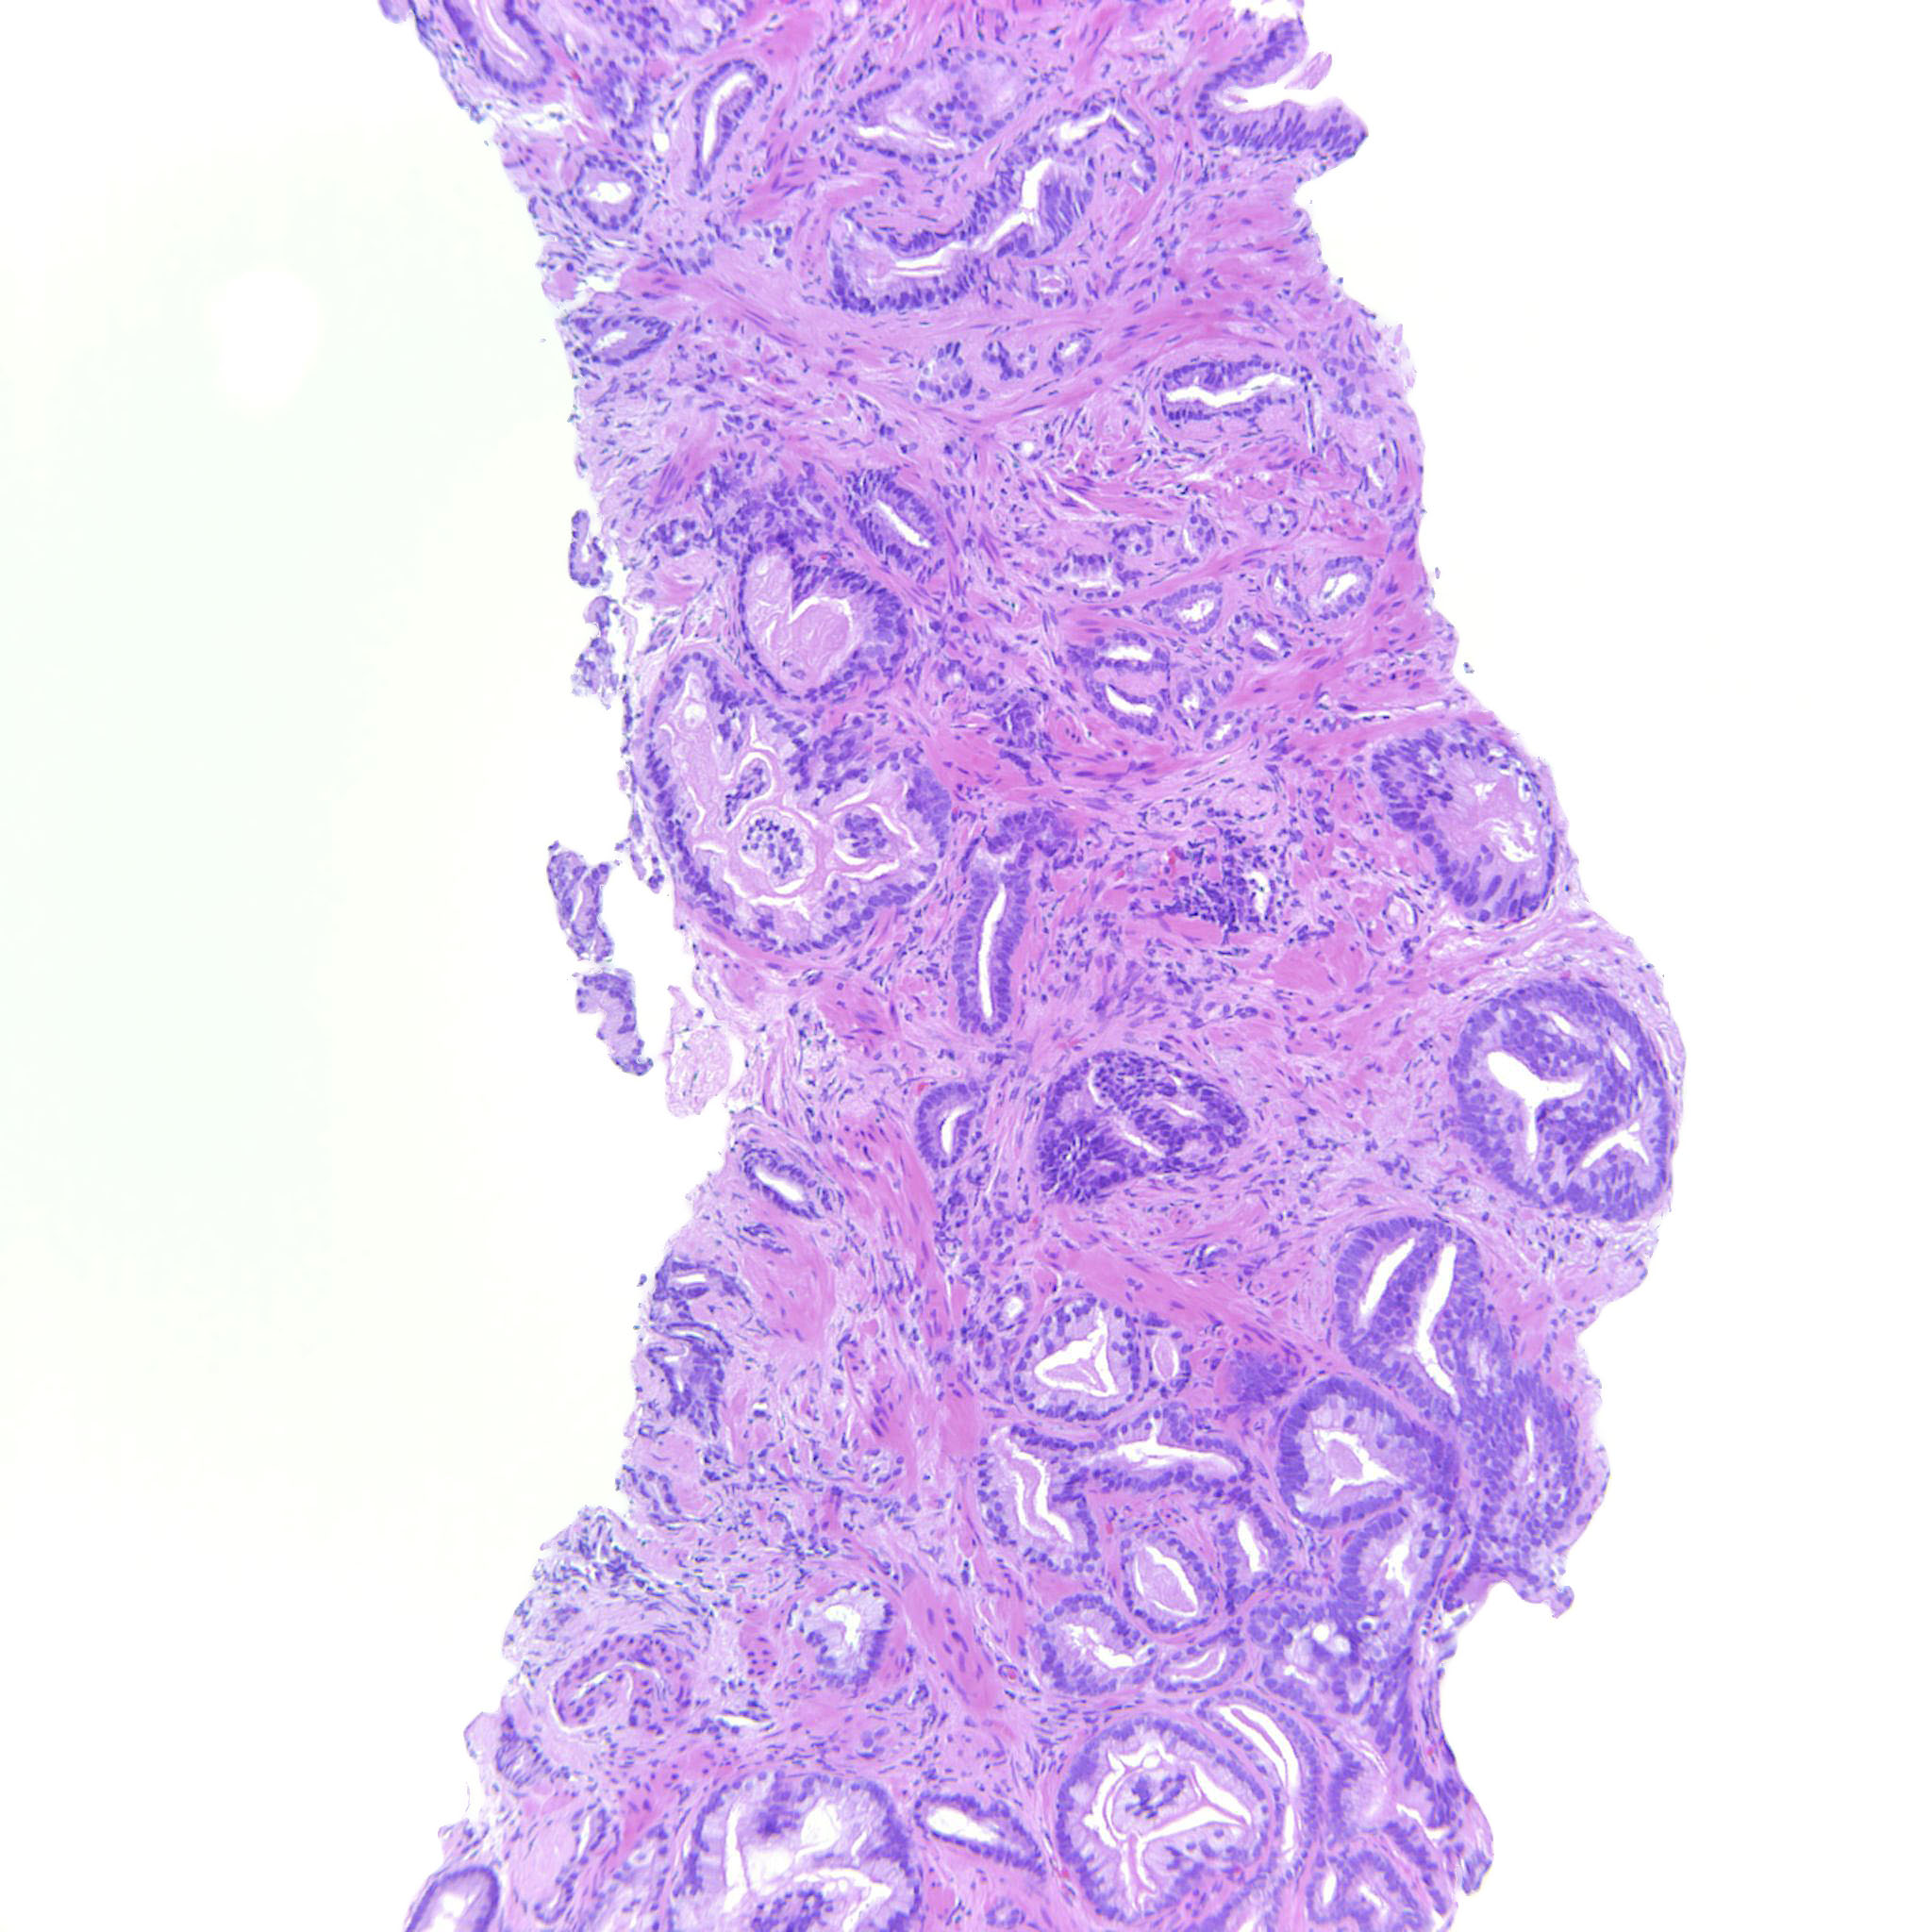

Prostate cancer grading

Case ID: 516